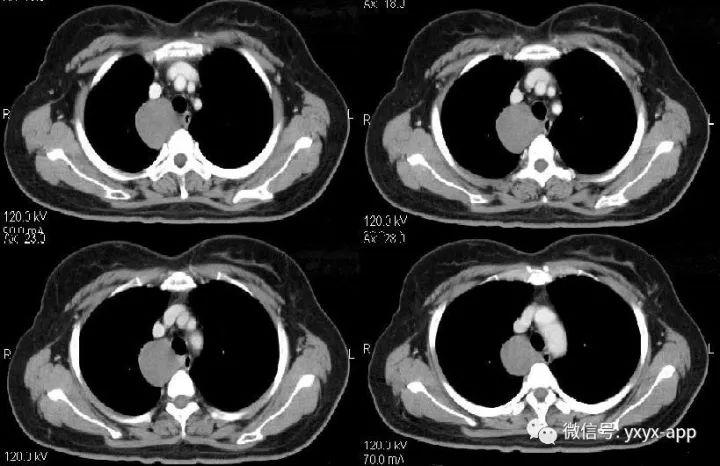

纵隔支气管囊肿1例CT影像表现

【基本资料】女,57岁

【主诉】胸疼、胸闷2月余

CT值在50-60hu之间

肚肚丫头:右上后纵隔、气管右旁、脊柱前方可见类圆形软组织密度影,与气管及食管均关系,增强后无明显强化,考虑囊肿,起源待定。

诊断:1.支气管囊肿;2.食管囊肿。鉴别诊断:神经源性肿瘤

【病理结果】支气管囊肿